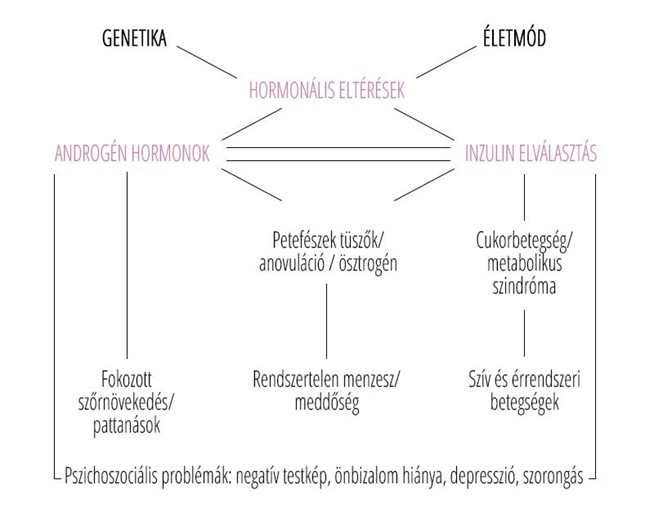

Az edukáció olyan fontos kérdéseket érint, mint: mi számít meddőségnek, mikor érdemes szakemberhez fordulni, hogyan hat az életkor a termékenységre, illetve milyen kockázatot jelentenek a szexuális úton terjedő fertőzések. Az iránymutatás külön kitér a legfontosabb kockázati tényezőkre, mint a dohányzás, a túlzott alkoholfogyasztás, az elhízás vagy éppen az alultápláltság, melyek mind kedvezőtlenül hathatnak a reproduktív egészségre. Ezzel szemben a kiegyensúlyozott, tápanyagokban gazdag étrend, a rendszeres testmozgás, valamint a dohányzás elhagyása bizonyítottan hozzájárulhat a termékenység megőrzéséhez és a későbbi problémák megelőzéséhez.